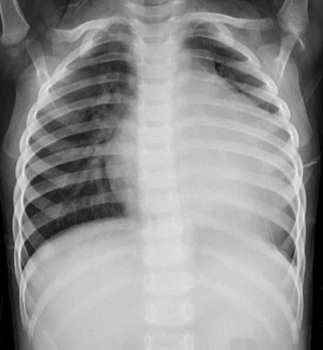

✦ Case 3,学龄儿童,急性心力衰竭、暴发性心肌炎

— 减轻心脏负荷:① 呋塞米 2mg/kg bid;② 氢氯噻嗪 2mg/kg bid;③螺内酯 2mg/kg bid ;④液量负平衡:每日负1000-1500ml

— 改善微循环:5%NaHCO3 1-2ml/kg

• 病程1年,期间3次因感染加重住院

复查CMR

• 儿童HF病因多由感染诱发,新生儿期常见的病因为先天性心脏病,婴幼儿及儿童期HF多为感染诱发的心肌炎、心肌病等

• CMR检查能够清晰显示心肌的情况并帮助医生判断预后,建议生命体征稳定的HF患儿行CMR检查,并定期随诊